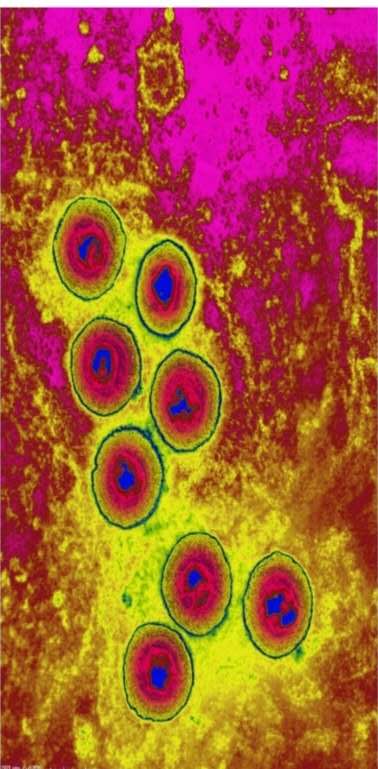

图5,艾滋病毒,右图左起:逆转录酶,糖蛋白,脂双层膜,整合酶,核心,RNA,蛋白质壳,蛋白酶。典型的有潜伏感染的病毒,潜伏期均有感染性。

艾滋病毒是典型的具有潜伏感染的病毒,其潜伏期为0.5—20年,平均7-10年才能发展到病毒原发感染。未发病的可长期甚至终身隐匿,成为艾滋病携带者。

处于潜伏感染的艾滋病感染者,其血液、精液、阴道分泌物、乳汁、脏器中均含有艾滋病病毒,具有传染性。

艾滋病毒潜伏感染的储存地是脑脊液,病毒在其中的巧妙手段是,当细胞DNA复制是,将自己的基因组整合的宿主细胞的基因组中,融为一体,长期潜伏。任何药物对它没有办法,只能听之任之。一当机会来临,病毒就会脱离细胞成为原发感染。这就是艾滋病毒在人体内长期存在的原因。可怕的是潜伏感染的艾滋病毒允许病毒传播。

图6,HIV潜伏在宿主脑脊髓炎液中,宿主终身携带